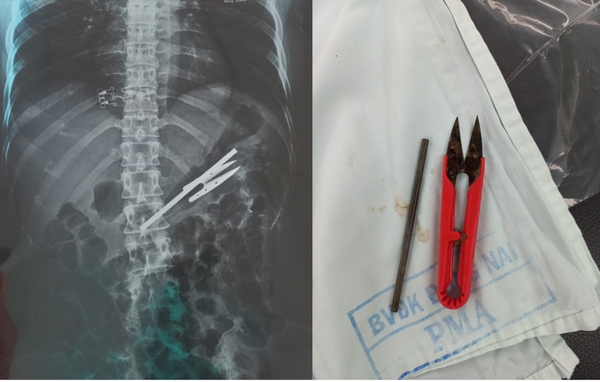

Đọc thêmQua chụp X-quang, phát hiện trong dạ dày bệnh nhân có 1 cây kéo cắt chỉ và 1 thanh kim loại. Các bác sĩ đã mất 1 giờ 30 phút nội soi mới gắp được các dị vật ra ngoài.